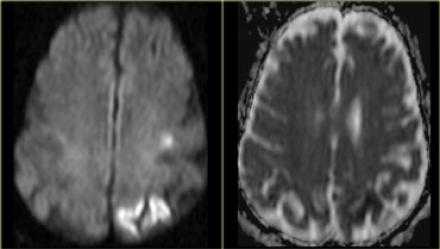

Ниже представлены изображения пациента, у которого были установлены неврологические проявления около часа назад. Постарайтесь выявить патологические изменения, а после продолжите чтение.

Данные изображения соответствуют норме, поэтому следует перейти к диффузно-взвешенному изображению. Взгляните на следующие изображения.

На DWI выявляется зона ограничения диффузии, и если после выполнения перфузии не будет выявляться зона перфузии, то следовательно нет смысла выполнять тромболизис.

На выше лежащих изображениях визуализируется инфаркт в бассейне СМА. На КТ четко визуализируются необратимые изменения. Далее представлены DWI и перфузия. При сопоставлении зон становится ясно, что не нужно выполнять тромболизис

При ознакомлении с перфузионными изображениями, то визуализируется несоответствие. В левом полушарии выявлена область гипоперфузии. Данный пациент абсолютный кандидат на тромболитическую терапию.